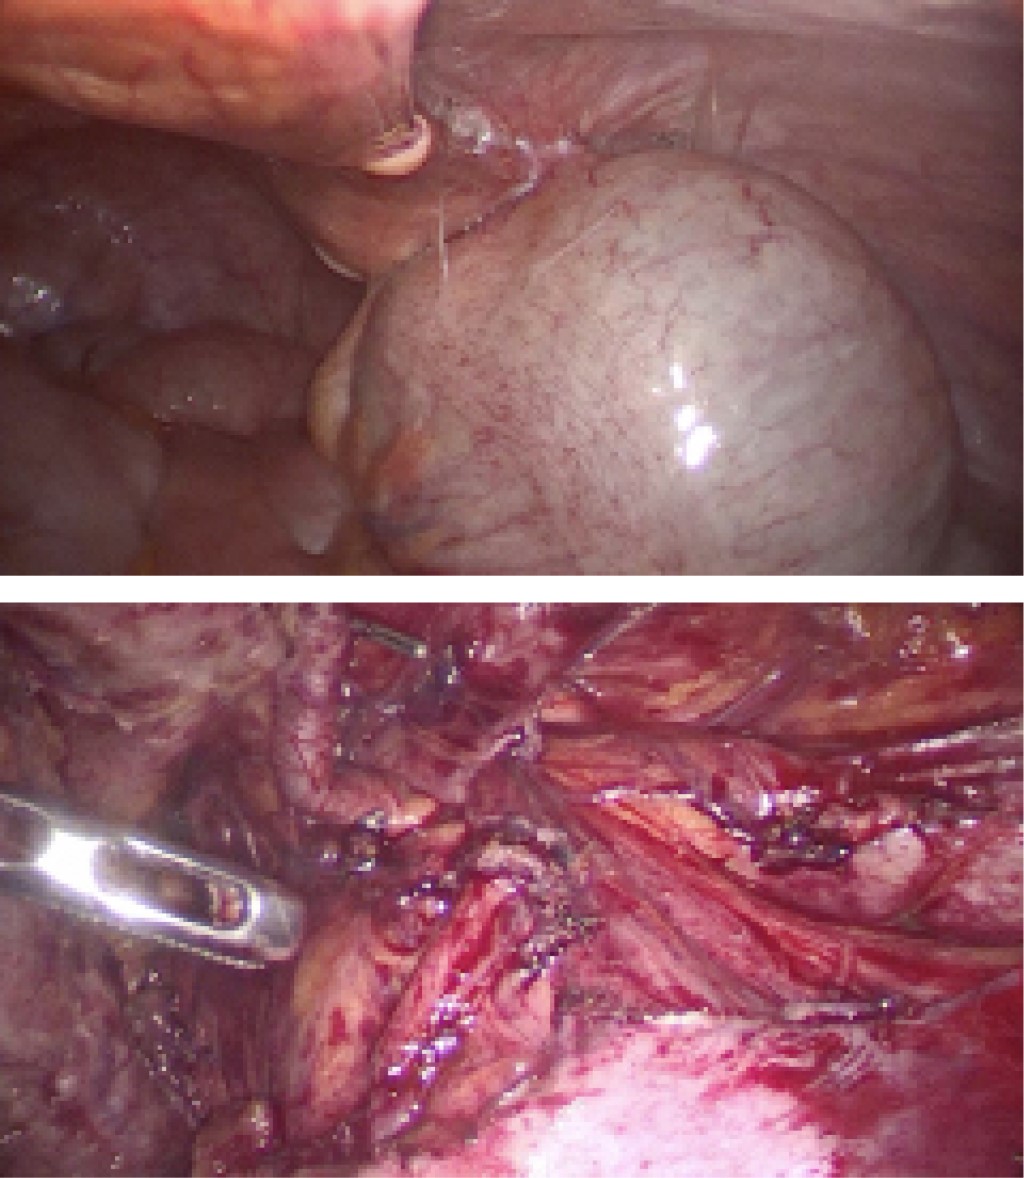

Introduction: appendicular neoplasms represent 1% of all colorectal cancers, one of the histological variants is appendiceal mucinous neoplasm, formerly known as mucocele. The clinical presentation is largely similar to that of acute appendicitis, so its preoperative diagnosis is rare. Clinically, patients present different symptomatology depending on the stage they are in, the most common manifestations are pain in the right iliac fossa, fever, palpable mass, abdominal distension, weight loss, anemia, chronic abdominal pain, infertility, among others. The defining pathologic characteristic of evidence of low-grade appendiceal mucinous neoplasm (LAMN) is invasion of the appendiceal wall, the presence of irregularity in the wall of the observed and the increase in thickness of the soft tissues can predict the malignancy of the tumor. Peritoneal involvement at the time of diagnosis can be up to 53%. The possibility of disease progression to pseudomyxoma peritoneal exists if dissemination occurs by rupture of the lesion and release of mucin into the peritoneal cavity. The treatment of LAMN always requires surgical management and the use of hyperthermic intraoperative chemotherapy in case of peritoneal involvement is still under debate. Case presentation: this case deals with a patient, 41 years old, who after three months with abdominal pain in the right iliac fossa, is taken to the operating room for a diagnostic laparoscopy due to the suspicion of a mucinous neoplasm, no mucinous lesions were found, an appendectomy plus cecectomy was performed. With stapler, pathology reported LAMN with serial involvement (pT4) and at six months a control laparoscopy with no evidence of mucinous lesions. The involvement of the serosa opened the discussion on whether hyperthermic intraperitoneal chemotherapy is necessary when there are no visible mucinous lesions and there was no mucin contamination. Conclusions: the literature to date has no clear evidence on the prognosis of this type of injury and whether it is useful or not. The challenge of this diagnosis will be to have a multicenter prospective study that allows the development of care protocols with strategic treatments.

Figure 2

Figure 3